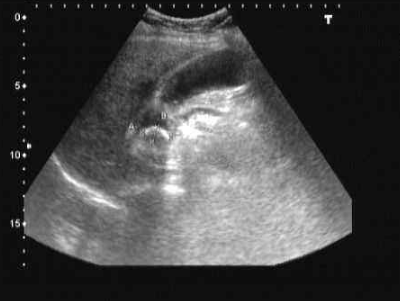

膽結石圖片

膽結石疼痛部位圖 (9)